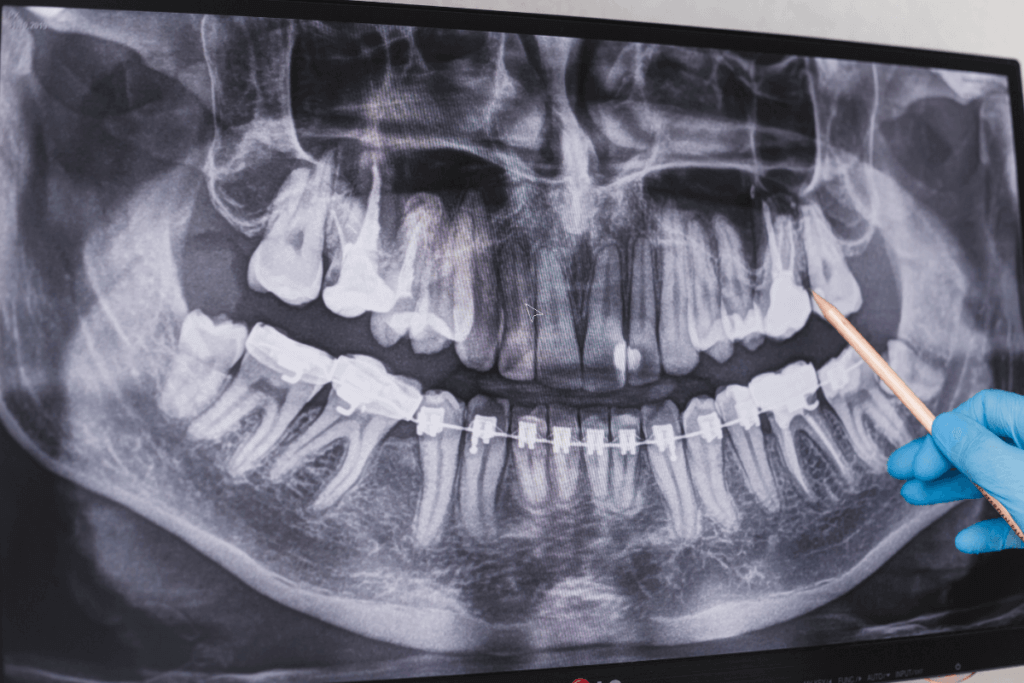

- Radiografia Digital

A radiografia digital é uma da tecnologia inovadora na odontologia muito importante e impactante na saúde bucal moderna. Substituindo gradualmente as radiografias convencionais de filmes, a radiografia digital oferece uma série de vantagens significativas para pacientes e profissionais da área.

A principal diferença entre a radiografia digital e a tradicional está na forma como as imagens são capturadas e processadas. Enquanto nas radiografias de filmes, o raio-x é registrado em películas sensíveis, as radiografias digitais utilizam sensores eletrônicos para capturar as imagens.

Esses sensores convertem os dados em sinais digitais, que podem ser visualizados em computadores e dispositivos eletrônicos.

Uma das principais vantagens da radiografia digital é a qualidade superior das imagens produzidas. Elas oferecem uma resolução mais alta, permitindo que os dentistas observem detalhes minuciosos da estrutura dentária e do tecido gengival.